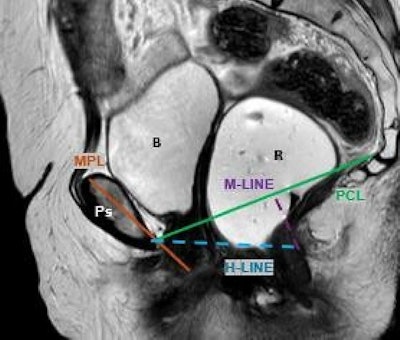

Sagittal T2-weighted MRD image at maximal pelvic floor contraction (squeeze). The pubococcygeal line (PCL) serves as a reference line extending from the inferior border of the pubic symphysis to the last coccygeal joint. The H line represents the anteroposterior dimension of the levator hiatus, while the M line measures the perpendicular descent of the levator plate relative to the PCL. The midpubic line (MPL) provides an additional reference for anterior-posterior alignment. Identifiable pelvic structures include the pubic symphysis (Ps), rectum (R), and bladder (B).Pugliesi et al; EJR